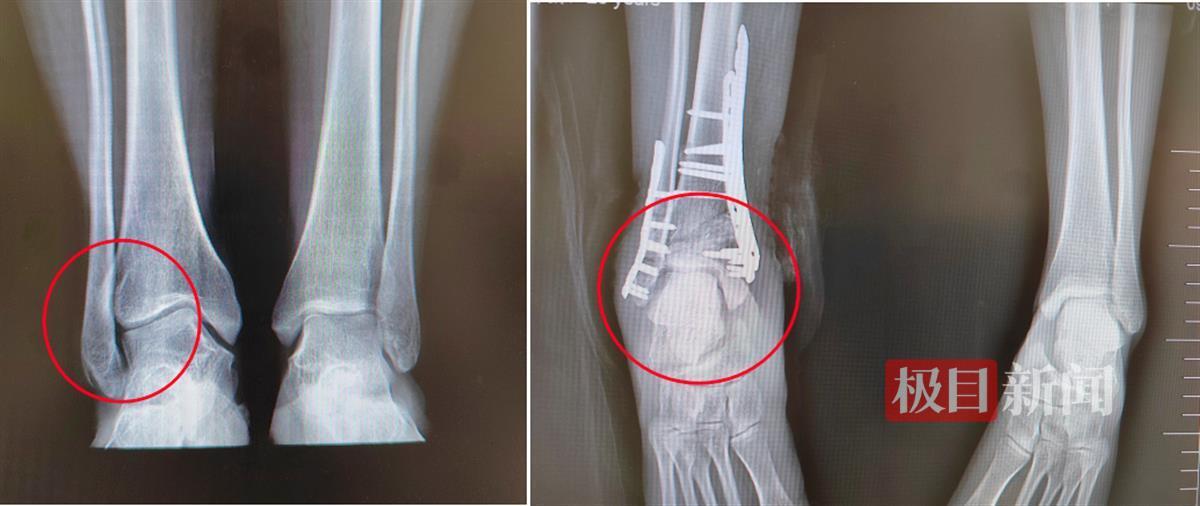

经沟通,患者决定手术矫正。术前,该院骨科团队进行了详细的评估和诊断,包括X射线和计算机断层扫描等,以确定畸形的类型、程度、影响范围和手术方式。日前,由吴大清主刀,为患者实施了踝关节内翻畸形截骨矫形植骨内固定术,即截骨矫形后取自身髂骨植骨、接骨板螺钉内固定术。

据介绍,手术主要分为三个步骤:截骨、植骨和内固定。在截骨步骤中,医生将外踝进行楔形截骨并稍短缩,以消除畸形和调整踝关节的位置,然后按术前测量角度及术中定位,进行胫骨远端360°截骨,并进行相应旋转。随后,在植骨步骤中,医生会取患者髂骨的内侧半板(保留髂骨的相对完整性),进行矫形后的骨缺损填充。最后,在内固定步骤中,医生会使用金属螺钉或钢板等器械将踝关节矫形后进行固定,从而实现“移花接木”的效果。手术矫形后患者力线恢复良好,踝关节距骨面负重均匀,预后行走无疼痛。

术前术后对比